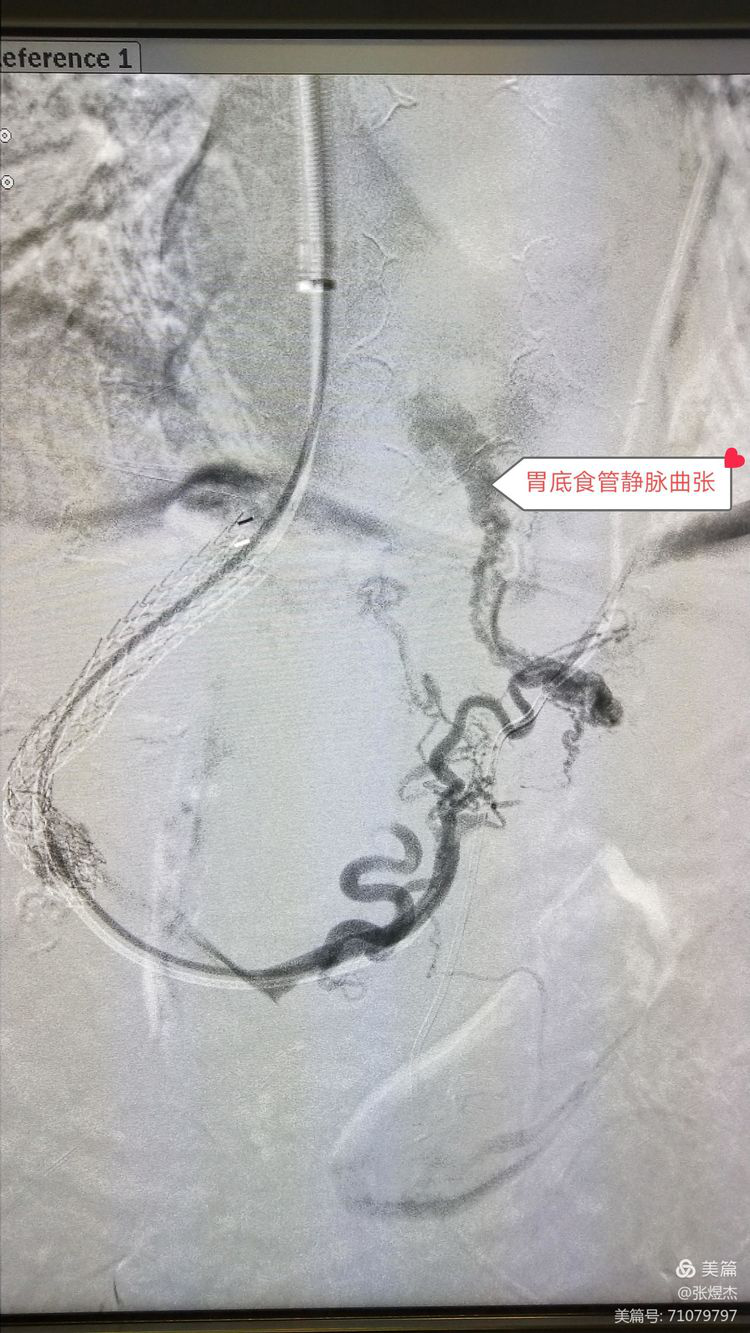

胃底食管静脉曲张的本因是,酒精肝、乙型肝炎性等其他原因导致肝硬化,肝小叶结构改变,门静脉终末枝变 异,进入肝组织的门静脉血流受阻导致门脉高压,胃底食管静脉血流回流受阻,憋涨增粗然后出血。所以肝硬化胃底食管静脉曲张破裂出血,就是急性呕血的一大病因。

建立门静脉和肝静脉分流通道,同时用弹簧圈栓塞曲张的胃底食管静脉,同时运用引黄入海加堵决口两个方法,杜绝胃底食管静脉出血导致上消化道大出血。